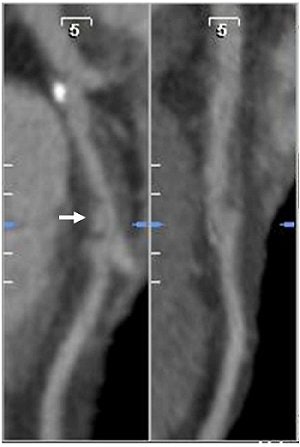

| Coronary CTA images (above) show extraluminal contrast in communication with the coronary lumen, consistent with a ruptured coronary plaque. An invasive angiogram (below) from the same patient showed extraluminal contrast (arrow) representing a ruptured plaque associated with a severe stenosis in the left anterior descending artery. Images courtesy of Dr. John Lesser and Dr. Jamie Pelzel. |